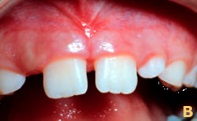

Caso 1

Freio Labial com divergência dos incisivos